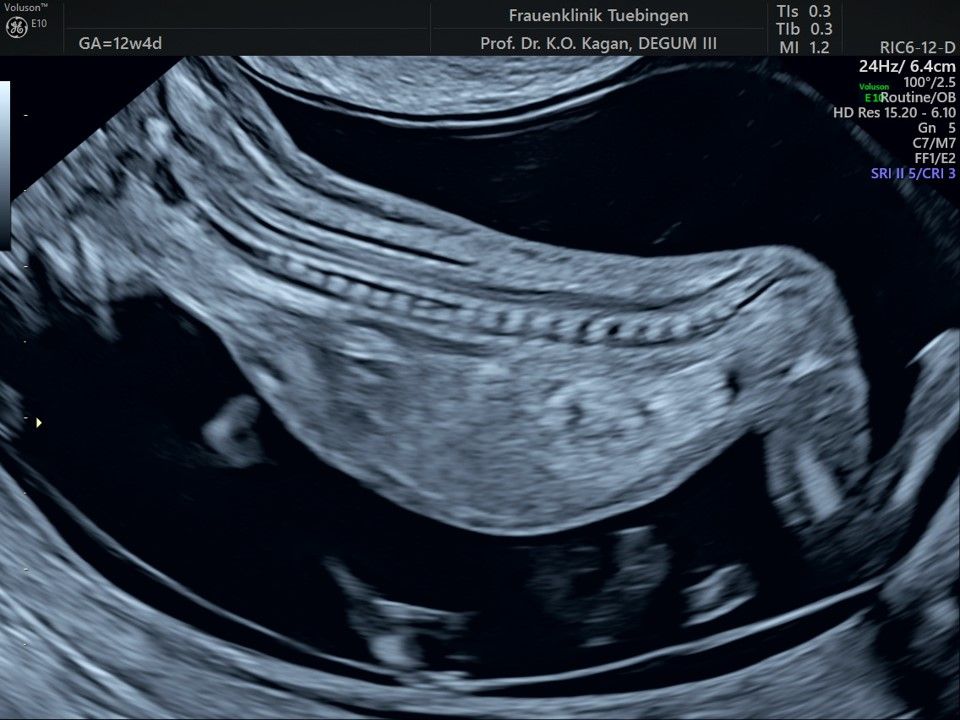

Das Ergebnis der Ultraschalluntersuchung ist wegweisend. Dabei wird der Fet vermessen, die Organe werden untersucht und die sonographischen Marker zur Risikoberechnung für Chromosomenstörungen werden beurteilt. Das sind: die Nackentransparenzdicke, Nasenbein sowie der Blutfluss in der rechten Herzhälfte und im Ductus venosus, einem Gefäß in der Leber des Feten.